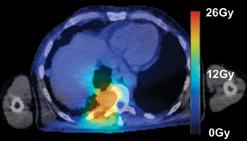

Images (left,1, & below): adoption of SBRT for spinal irradiation to nonspinal bone metastases (2, 4) standard AP/PA (1, 3)

Our current workflow for same-day palliation requires three to four hours and is a highly coordinated conventional workflow with kVCT simulation, treatment planning, treatment plan quality assurance and then treatment delivery. During treatment planning, TomoHelical or TomoDirect delivery mode is chosen, along with 3-D or intensity-modulated radiation therapy (IMRT) planning mode. We employ dosimetric concepts from stereotactic body radiation therapy (SBRT) to deliver a highly conformal target dose distribution, while minimizing dose to adjacent normal tissues. We generally employ an extreme hypofractionated palliative regimen consisting of 8 Gy per fraction with one to three fractions, depending on tumor size, tumor location, dose to normal tissues and patient-specific goals.